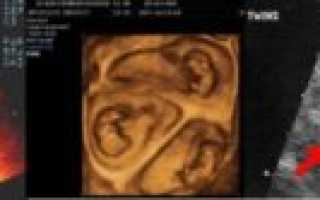

4. Ультразвуковое исследование — самый достоверный способ увидеть и определить, какая у женщины беременность, более точный срок беременности, размеры плодов и все патологии, существующие у двоих эмбрионов (если таковые имеются). А также при помощи данного метода возможно определить однояйцевая или разнояйцевая беременность наблюдается у женщины.

Двойню на УЗИ можно увидеть и определить уже на 4-5 неделе беременности. Как правило, однояйцевые близнецы определяются позже, чем разнояйцевые (не раньше 12 недели).

Самый верный способ выяснить количество эмбрионов – это дождаться первого УЗИ. В муниципальных женских консультациях оно проводится на 12 – 14 неделях во время первого скрининга.

Самый ранний срок, когда по УЗИ различим плодный мешочек – это 4 недели и 3 дня при условии, что менструальный цикл женщины 28 – 30 дней. Но двойню пока никакой аппарат не определит. Это возможно лишь на 8 акушерской неделе.